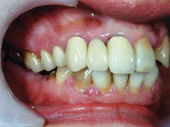

40歳代前半の女性の患者さんの場合下顎の左右の奥歯がありません。

虫歯で大臼歯を失ってから約5年間、そのままの状態(奥歯を抜いたままの状態)を放置してきてしまいました。

左右の下に大臼歯と呼ばれる奥歯が4本有りません。長期間歯の無いまま放置してきてしまったので左右の上の奥歯が下方に挺出(歯牙が合対する無くなってしまった歯の方へのびてくる現象)。

このままの状態ではインプラントが入れられません。

正面から見ると、上の奥歯が下にのびているのがわかります。

このままさらに放置しておくと、そのゆがみは前歯へと及び、さらに広範囲な全顎的な歯科治療を行わなくてはなりません。

この様に挺出(上の奥歯が下方にのびる現象)してしまった上の奥歯は新たに削って被せ物クラウンにするか、矯正歯科治療を全顎的に行い、上下歯の咬合、噛み合せの状態を修正しなくてはなりません。